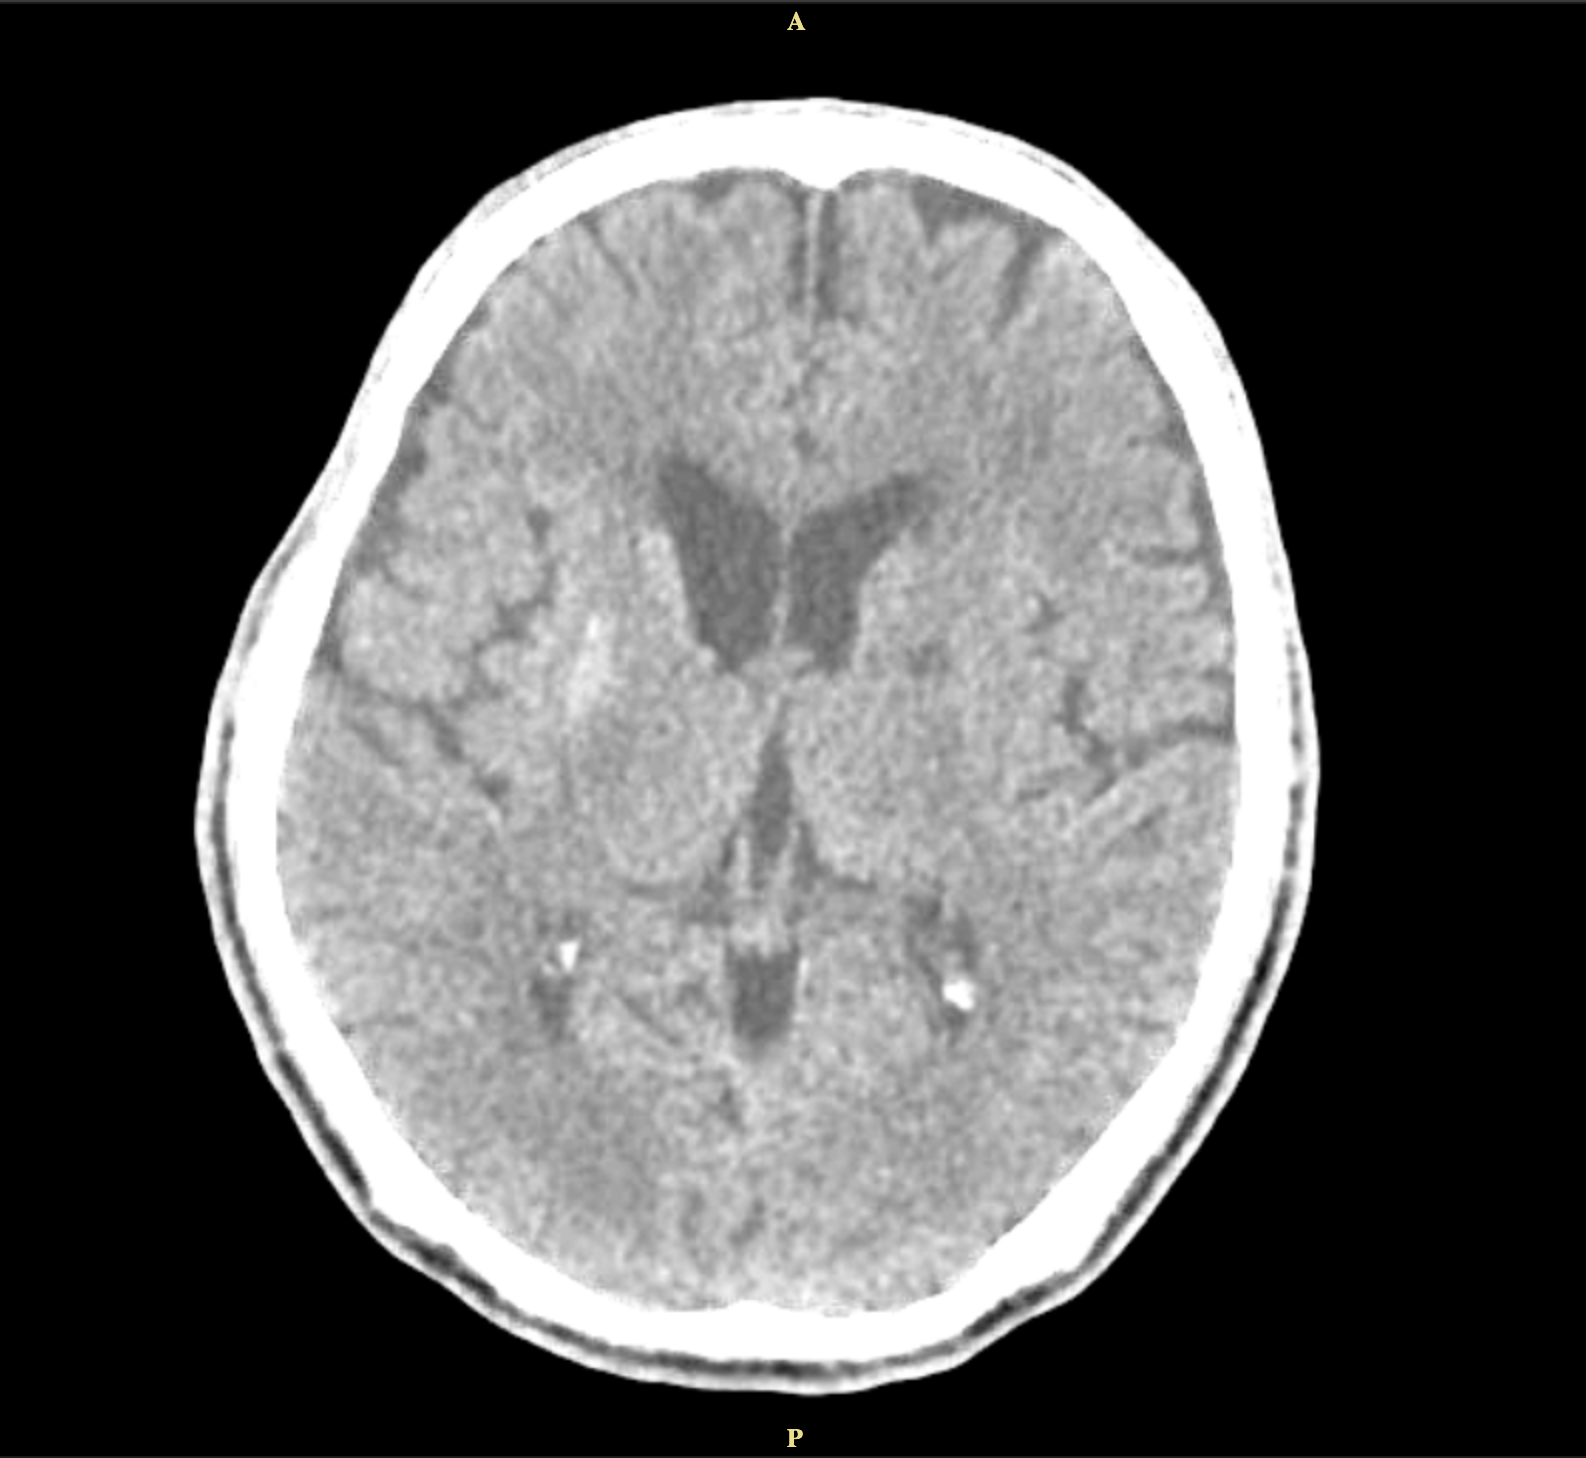

Method: A 62-year-old man with uncontrolled diabetes presented with left-sided involuntary movements and slurred speech. His blood glucose was elevated at 576mg/dl, and CT imaging showed hyperdensity in the right caudate and lentiform nuclei. His condition improved with glycemic control, and antichoreic medications were not needed.

Results: This condition occurs in about 1 in 100,000 individuals. Diagnosis relies on neuroimaging, particularly CT or MRI, which reveal basal ganglia lesions, often in the putamen or caudate nucleus. The hallmark finding is striatal hyperintensity without mass effect, sparing the internal capsule. CT has a sensitivity of 78%, and MRI 95% for detecting diabetic striatopathy, with resolution times ranging from 10 to 60 days.

Conclusion: The classic triad for diabetic striatopathy includes poor glycemic control, unilateral striatal hyperdensity on CT imaging, and contralateral choreic movements. Treatment involves achieving euglycemia and managing chorea. Symptom resolution can occur within 2–14 days, with glycemic control alone resolving symptoms in 25% of cases. Adding anti-choreic medications increases resolution to 76%. He continued intensive insulin therapy for 6 months, leading to improvement and eventual resolution of left-sided movement.

Figure 1.3